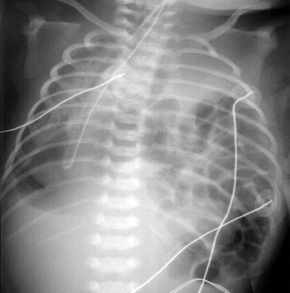

Hérnia diafragmática congênita

Do acervo de Ponthenkandath Sasidharan, MD; usado com permissão